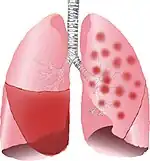

| Typical distribution of lobar pneumonia (left in image) and bronchopneumonia (right in image) | |

On gross pathology there are typically multiple foci of consolidation present in the basal lobes of the human lung, often bilateral. These lesions are 2–4 cm in diameter, grey-yellow, dry, often centered on a bronchiole, poorly delimited, and with the tendency to confluence, especially in children.